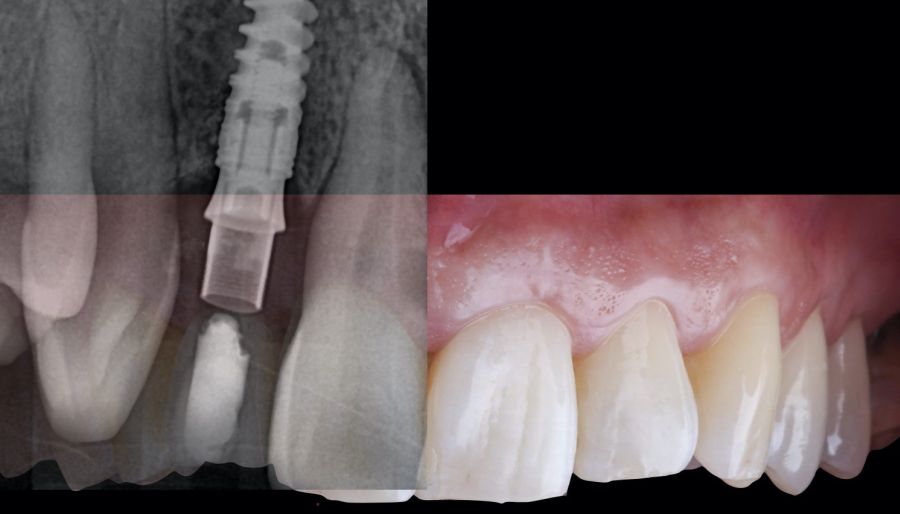

* Phase II: healing proceeded without complications. After 5 months from the alveolar preservation surgery, guided implant surgery was planned at position 1.2 (Figure 2). For this purpose, a DICOM file from cone beam computed tomography (CBCT) and an STL file obtained from scanning with an intraoral optical scanner were used. Using this information, a dental support surgical guide was fabricated (Figure 3). The surgical guide was anchored onto the teeth and guided the preparation of the implant bed and the placement of the implant. The guided surgery technique consisted of flap surgery, preparing and inserting the implant (3.5 x 11.5 mm) according to the standardised Nobel Active® guided surgery protocol (Nobel Biocare AB, Gothenburg, Sweden). Once implant 1.2 was placed,a gingival graft composed of epithelium and connective tissue from the palatal masticatory mucosa was obtained. Subsequently, the superficial epithelial layer of this graft was deepithelialised extraorally using a 15C scalpel blade in order to obtain a connective tissue graft from the underlying layer18.

The de-epithelialised graft was inserted and

positioned buccally and occlusally using horizontal mattress sutures with 5-0 non-resorbable suture (Figure 4)19.

* Phase III: three months after implant placement, the soft tissue condition was favourable (Figures 5 and 6). A digital impression was obtained using an intraoral scanner for the fabrication of a screwretained